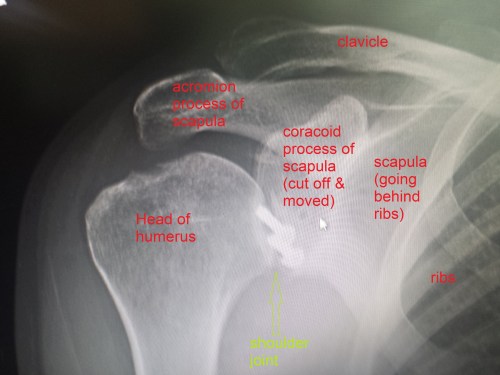

It has been almost three months since my last post here, and things have fallen quiet on our sister blog Anatomy to You, too. I thought it was time for an update, which is mostly a summary of stuff we’ve been doing on my team, but also featuring some interesting images if you stick around. The relative silence here has partly been due to me giving myself some nice holiday time w/family in L.A., then having surgery to fix my right shoulder, then recovering from that and some complications (still underway, but the fact that I am doing this post is itself evidence of recovery).

X-ray of my right shoulder from frontal view, unlabelled

Labelled x-ray